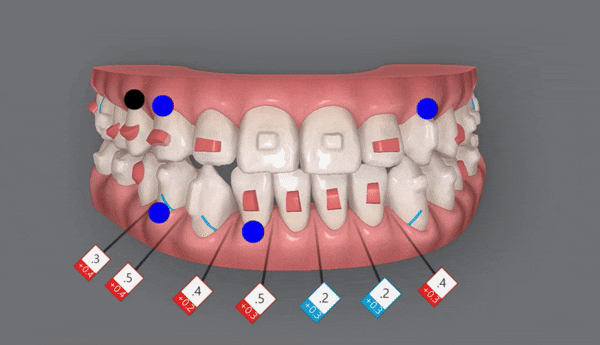

1st(46개)

인비절라인의 장점 중의 하나는

교정 후의 모습을 예측할 수 있는것 입니다.

원장님께서 클린체크 디자인을 마치게 되면

인비절라인 교정치료 후에

치아이동이 어떻게 변화하는지 클린체크를 통해 확인 해 볼 수 있는것인데요.

클린체크대로

치아들이 움직이면서 점점 가지런해 지는게 보이시나요?

첫번째 클린체크에서는 잠실교정치과 유펜바른치과에서 총 46개의 장치로

진행 해드렸습니다.

악궁이 점점 확장되면서 삐뚤빼뚤했던 치열들이 가지런하게 배열되고,

윗니 아랫니 사이의 공간이 점점 닫히며,

반대교합이 개선되면서 정상적인 교합으로

변하고 있는 모습을 확인해 보실 수 있습니다 ^^